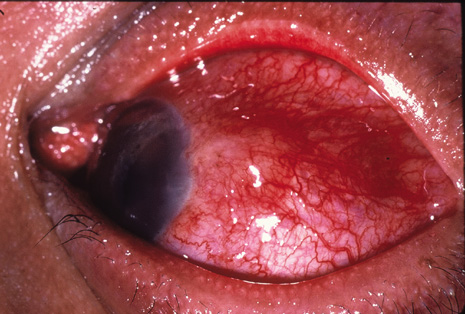

Although keratocentesis had been advocated historically as a treatment for active uveitis, it lost the attention of ophthalmologists until 1919, when Bruckner3 first examined the aqueous humor for diagnostic purposes. Laboratory techniques were revolutionized in the 20th century in areas such as: (a) evaluating very small aliquots of fluid (0.2 to 0.3 mL of aqueous or vitreous), and (b) identifying specific microbial organisms and the predominance of other cell types, antibodies, and proteins in these fluids (Figs. 1, 2, 3, 4, 5, and 6). These advancements have led to the development of diagnostic paracentesis for sight-threatening ocular inflammations that are difficult to diagnose. Witmer4 and O'Connor5 have provided strong evidence that samples of the aqueous humor reflect the antibody-producing capabilities of the iris and ciliary body, particularly when more specific antibody per unit of gamma globulin can be found on the aqueous humor than in the blood of the same patient.6–8 These determinations may be highly significant when one considers the fact that diseased tissue is being bathed in an antibody-containing fluid that is elaborated locally. For instance, in the case shown in Figure 1, the immunofluorescent antibody titer to toxoplasmosis is four times greater in the vitreous aspirate at the time of vitrectomy for repair of retinal detachment than in the plasma. These same considerations have long been recognized in syphilis of the central nervous system, wherein specific antibodies may be present in the cerebrospinal fluid but not in the blood. This is also the case with an unusual presentation of ocular coccidioidomycosis9 or toxocariasis.

Many forms of uveitis are characterized by specific types of inflammatory cells. Usually, however, one encounters mixtures of cell types in any given specimen, with the relative percentages of lymphocytes and polymorphonuclear leukocytes varying. There may be unusual numbers of eosinophils, or macrophages laden with lens material may be present. Thus, an enumeration of the cells and a careful analysis of their structure can be useful as a diagnostic aid (Figs. 7, 8, 9, 10, 11, 12, 13, 14, 15, 16, 17, 18, 19, and 20). Figure 15 demonstrates eosinophils that were aspirated from the anterior chamber of a patient with Toxocara canis endophthalmitis. Figure 12 demonstrates malignant cell infiltrate from the vitreous, showing the stained presence of monoclonal light chains being elaborated in the cytoplasm. Interleukin-10, detectable in the vitreous of intraocular lymphoma patients, is also directly indicative of both the clinical activity and the number of malignant cells as observed by cytopathology.

Precise identification and culture of bacterial and fungal pathogens from both the aqueous humor and the vitreous fluid can be obtained. Gram's stain and Giemsa's stain smears of centrifuged specimens from the aqueous humor and the vitreous humor frequently demonstrate the bacterial or fungal causative agent. Attempts to isolate bacteria and fungi and to identify them on Gram's stain or Giemsa's stain smears have been most rewarding in the following cases: (a) postoperative endophthalmitis, (b) infection after a penetrating injury of the eye, (c) drug abuse patients with endogenous endophthalmitis (Figs. 21, 22, 23, 24, and 25), (d) patients receiving hyperalimentation, and (4) patients who are immunocompromised as a result of exogenous immunosuppressive agents.

Studies have demonstrated the usefulness of ocular paracentesis for the identification of ocular infections in order to implement sight-saving treatment.10–16 Even acid-fast bacilli and viruses may be diagnosed in this fashion when emergency dictates (see Fig. 5).17 It is recommended that diagnostic paracentesis be performed in all cases of postoperative endophthalmitis, and it is safe to perform the postoperative procedure in the operating room with the safety of vitrectomy surgery. Further, any patient older than 65 who presents with a deteriorating uveitis (usually with vitreitis as the predominant infiltrate) of undetermined etiology should undergo paracentesis of the vitreous to rule out reticulum cell sarcoma (large cell lymphoma).18 Similarly, any patient suspected of being an intravenous drug abuser who presents with an endogenous endophthalmitis or uveitis should undergo diagnostic paracentesis to avoid allowing an intraocular infection to be borne by the bloodstream.19,20